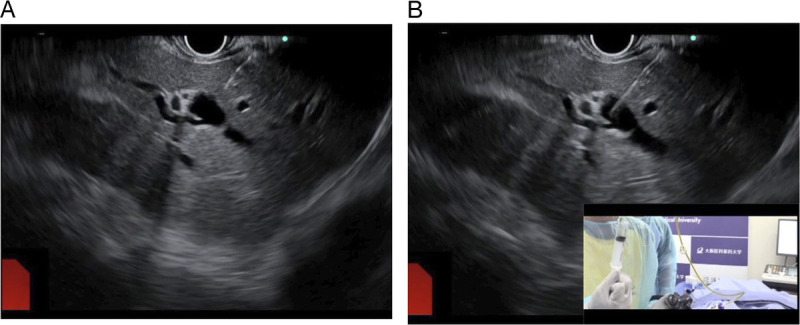

Technique tips for fitting alignment of puncture route during EUS-guided hepaticogastrostomy (with video).

在 EUS 引导下进行肝胃造口术时对准穿刺路径的技巧提示(附视频)。